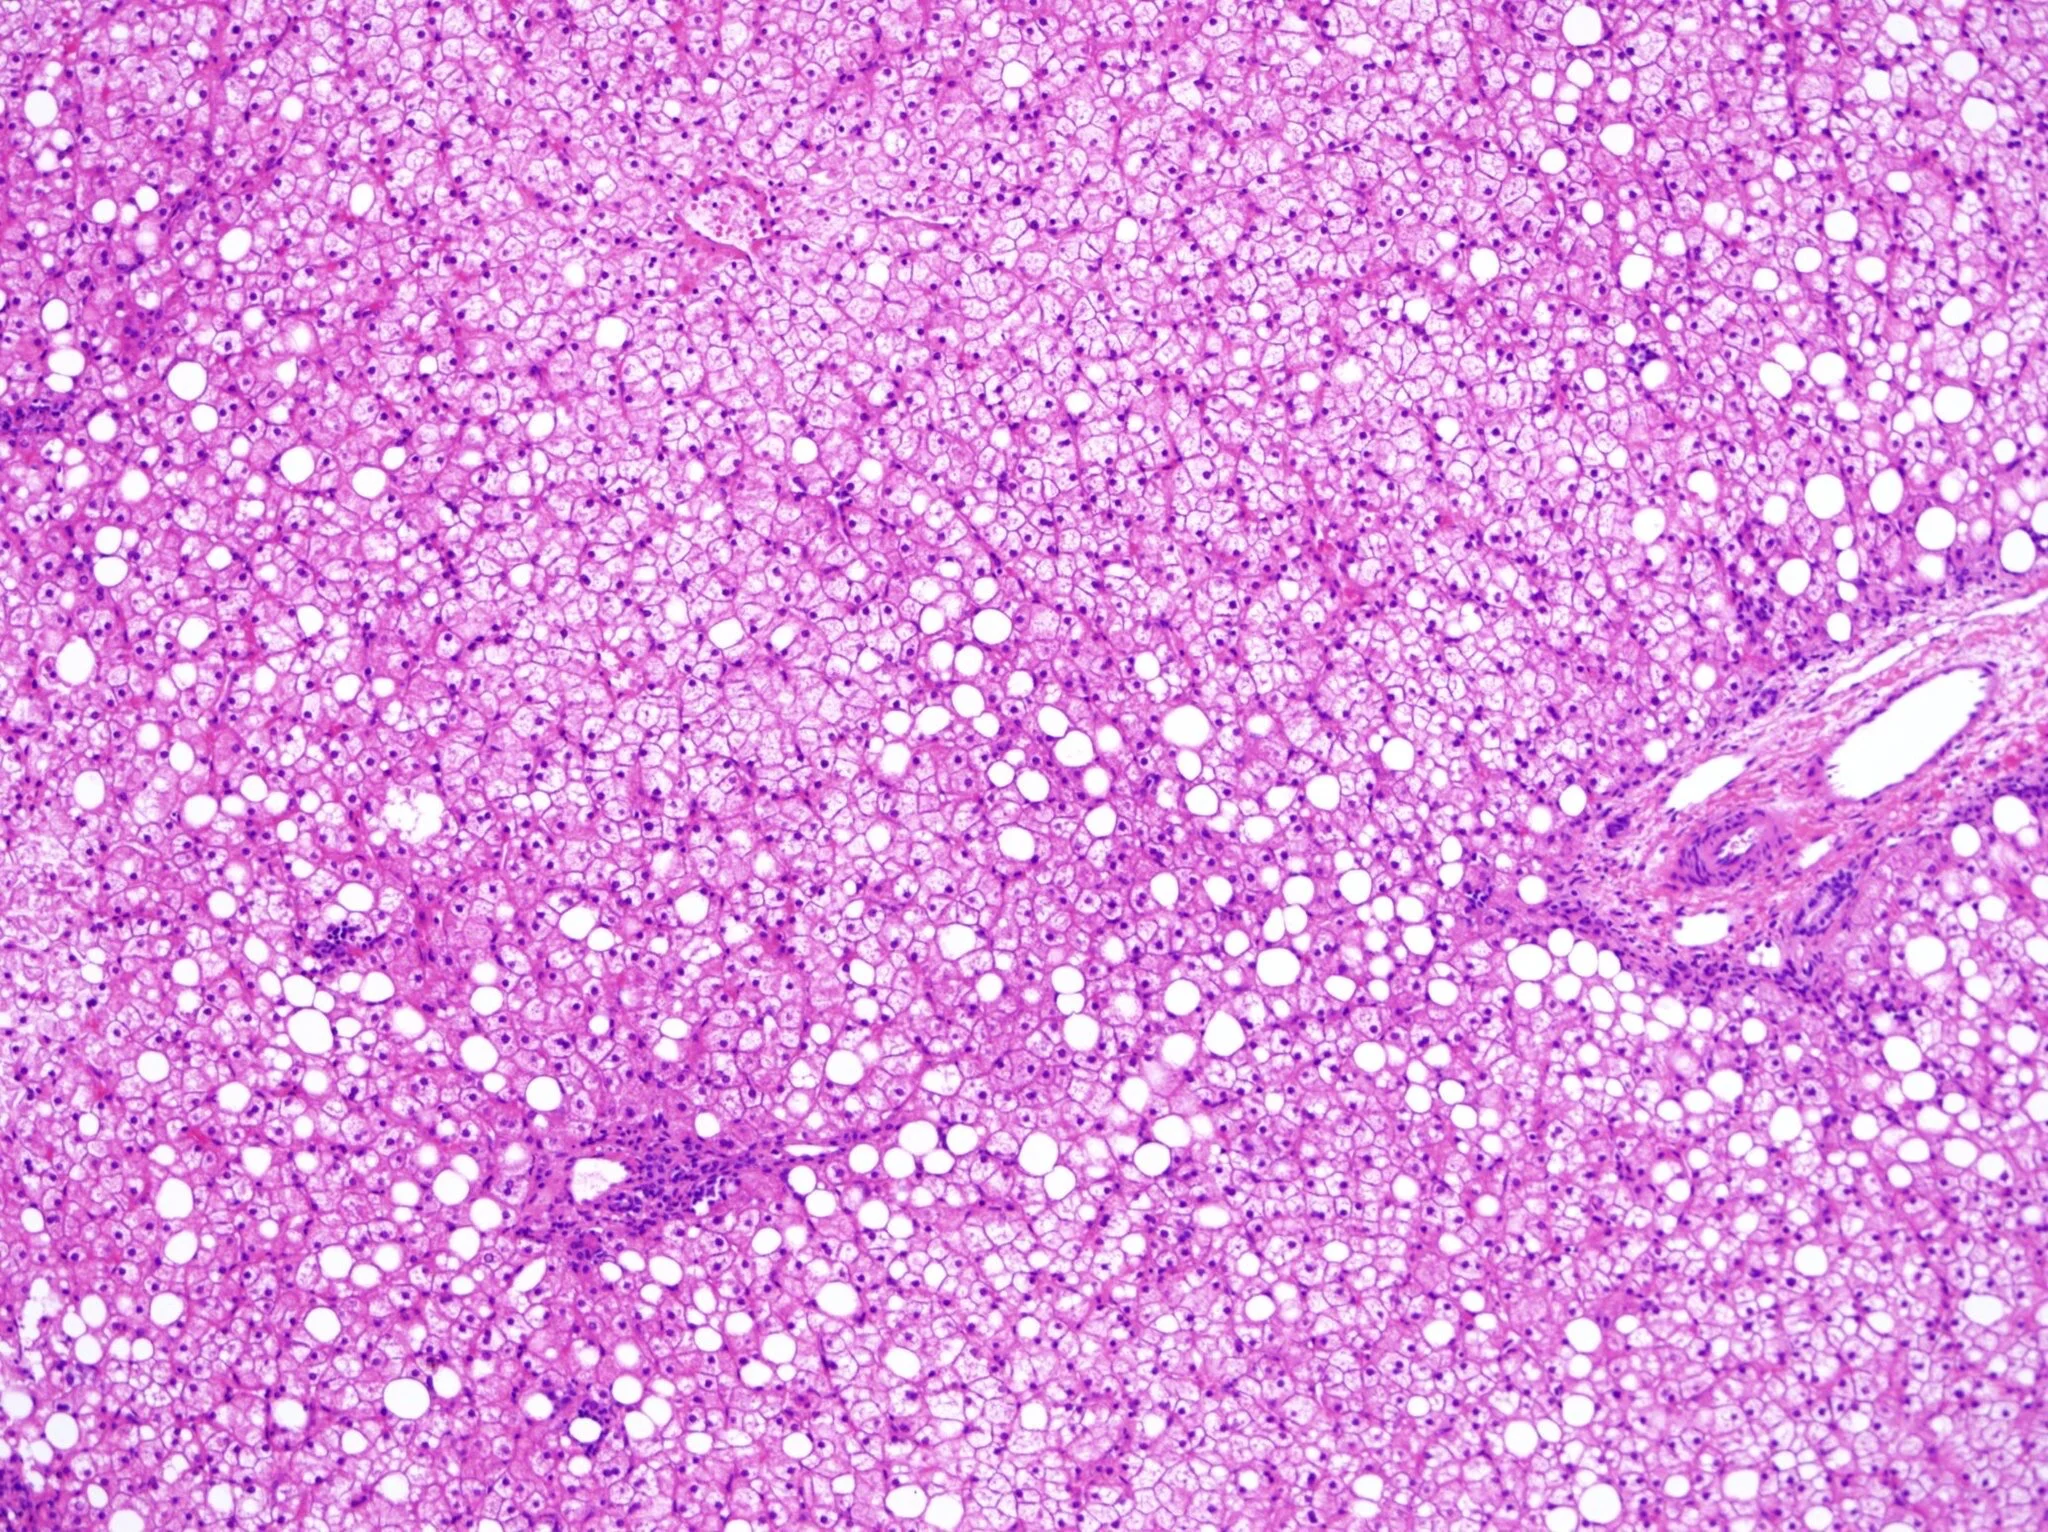

Histopathologic Features Of NAFLD And NASH Are: Steatosis (From 5% Of Hepatocytes) And Additional Changes Such As Lobular Inflammation, Hepatocellular Ballooning And Necrosis, The Presence Of Mallory-Denk Bodies And Pericellular Fibrosis.